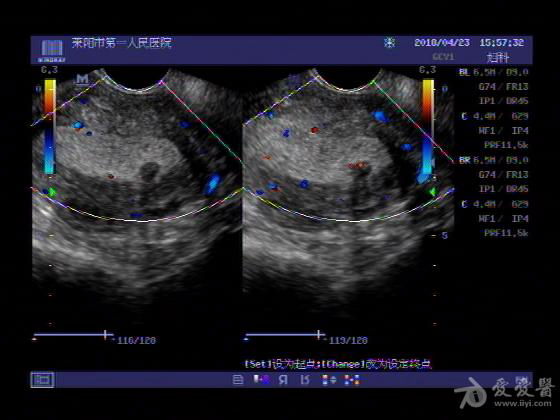

女,48岁,月经量多,两个月,一年前出现过类似现象,刮宫吃药后缓解。

超声可见:子宫内膜显著增厚,后肌壁内膜可见范围约3.27X0.90CM低回声区,CDFI显示较丰富线样血流,宫底宫腔内见类**状低回声结节。前肌壁见多发类圆形低回声结节。

超声提示:子宫内膜增厚(建议刮宫病理),子宫多发肌瘤

病理结果:内膜增生